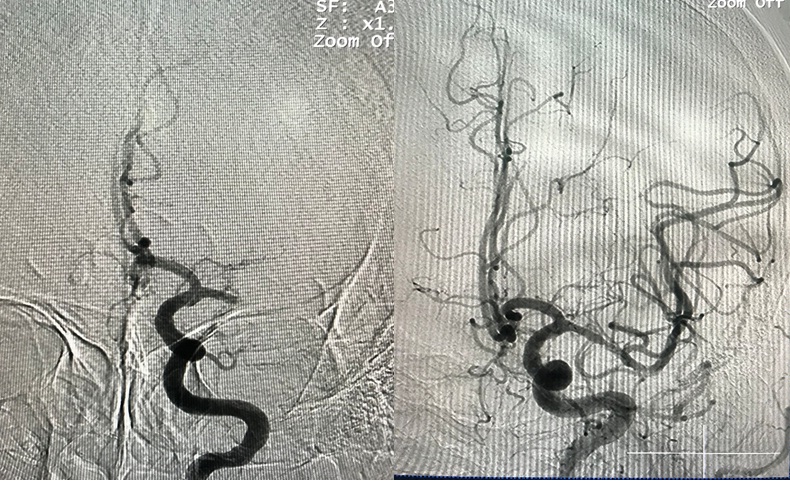

Hình: ĐM não giữa trái trước và sau lấy huyết khối